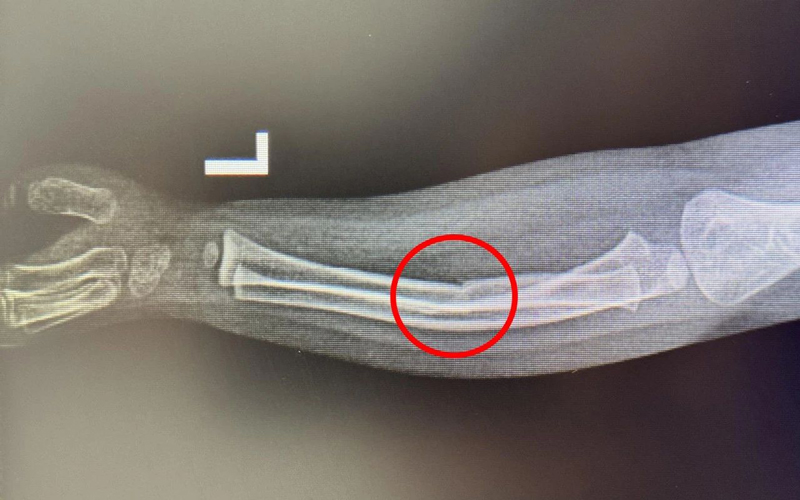

患者小徐今年16岁,因在学校不慎撞伤导致右手肿痛难忍来院就诊,穆中杰教授与科室医生认真研判病情,考虑患者为掌骨骨折可能,经过检查显示右手第5掌骨颈骨折,又称“拳击手骨折”,是临床上比较常见的手部骨折。

同患者及其家属进行沟通,决定行手法复位+杉树皮夹板固定,同时使用金黄散外用消肿止痛治疗,复位后骨折基本达解剖复位,患者及家属十分满意。

之后建议患者5-7天来我院复查,但患者因学业繁忙,于某小诊所行换绑调整夹板,导致骨折移位。

遂再次就诊于我院,经穆教授手法复位后,检查显示骨折复位良好。

温馨提示:骨折复位调整需谨慎,2-3周内易发生骨折移位,一般建议于正规医院行复查调整更为妥。